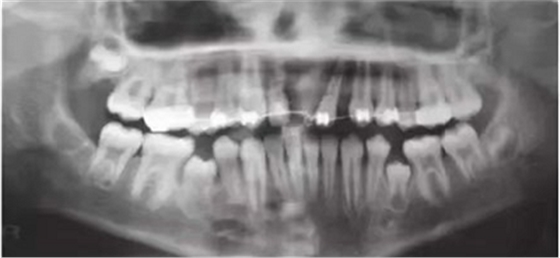

車禍后,一名10歲男孩被送往Shariati醫(yī)院急診科。診斷出上頜中切牙的脫落和側(cè)切牙的嵌入(圖1)。脫落的中切牙丟失了,沒(méi)有進(jìn)行再植。全景片示除第二磨牙外的恒牙列(圖2)。

【病例分享】上頜中切牙區(qū)外傷的自體移植和正畸治療

圖1. 初診口內(nèi)照

圖2. 初診全景片